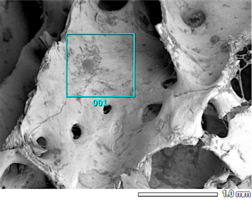

Биоимплантаты аллогенные стерильные губчатые механически и и ультразвуком обработанные.

Фрагмент правильной формы неоднородной поверхности без дополнительных включений и субстанций натурального или синтетического происхождения.

По внешнему виду представляет собой пористый губчатый блок номинального размера.

2. Поверхность и структура материала для изготовления биоимплантатов